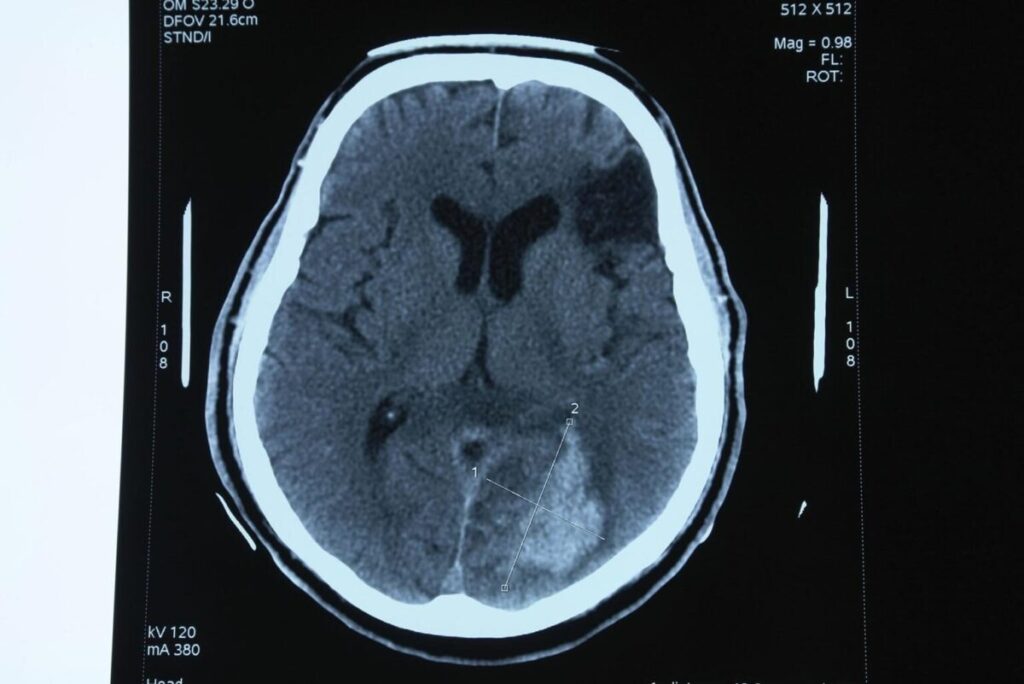

② CT(コンピュータ断層撮影)1972

発明者

ゴッドフリー・ハウンスフィールド

アラン・コーマック

原理

X線をコンピュータ処理し脳の断面画像を作る。

意義

脳腫瘍、脳出血などを生体で診断可能にした。